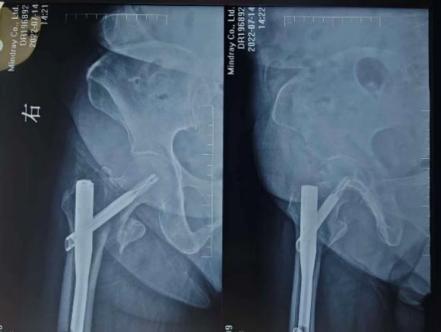

骨折X线片及CT

2022年6月,68岁的谈大妈不慎摔伤,导致右侧股骨粗隆间骨折,在当地一家医院接受了内固定手术。然而术后她的康复之路并不顺利——右髋持续疼痛,卧床三个月后尝试下地,发现每走一步都如同踩在针尖。就这样持续一年后,她因剧痛彻底无法行走,生活完全不能自理,整个人的状态瞬间跌入谷底。

第一次内固定术后X线片及CT